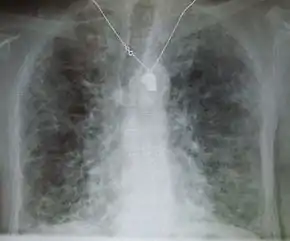

X-rays

Chest radiography is usually the first test to detect interstitial lung diseases, but the chest radiograph can be normal in up to 10% of patients, especially early in the disease process.[14][15]

High resolution CT of the chest is the preferred modality, and differs from routine CT of the chest. Conventional (regular) CT chest examines 7–10 mm slices obtained at 10 mm intervals; high resolution CT examines 1–1.5 mm slices at 10 mm intervals using a high spatial frequency reconstruction algorithm. The HRCT therefore provides approximately 10 times more resolution than the conventional CT chest, allowing the HRCT to elicit details that cannot otherwise be visualized.[14][16]

Radiologic appearance alone however is not adequate and should be interpreted in the clinical context, keeping in mind the temporal profile of the disease process.[14]

Interstitial lung diseases can be classified according to radiologic patterns.[14]